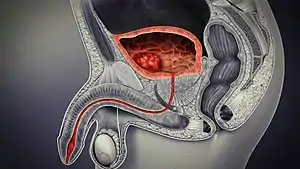

Bladder location and associated structures in the male

In men, the prostate gland lies outside the opening for the urethra. The middle lobe of the prostate causes an elevation in the mucous membrane behind the internal urethral orifice called the uvula of urinary bladder. The uvula can enlarge when the prostate becomes enlarged.

The bladder is located below the peritoneal cavity near the pelvic floor and behind the pubic symphysis. In men, it lies in front of the rectum, separated by the recto-vesical pouch, and is supported by fibres of the levator ani and of the prostate gland. In women, it lies in front of the uterus, separated by the vesico-uterine pouch, and is supported by the elevator ani and the upper part of the vagina.[8]